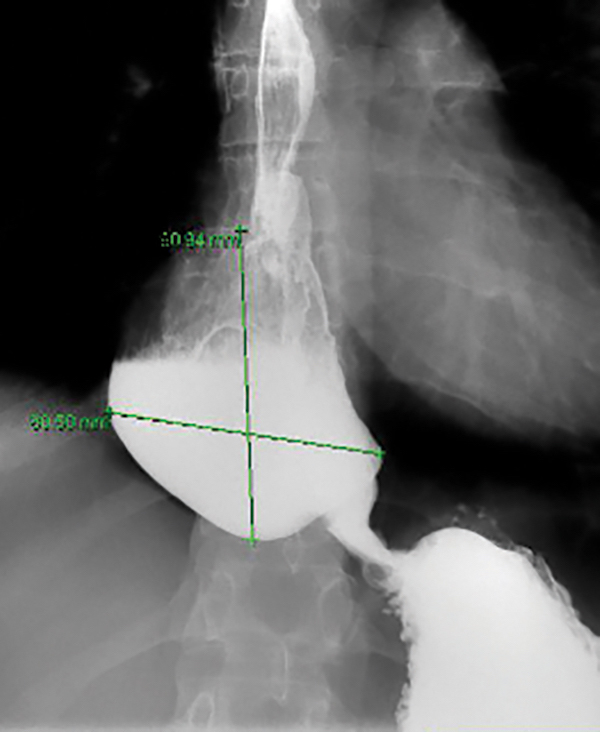

A 32-year-old woman who was diagnosed with type II achalasia 36 months ago underwent a Heller myotomy with a Dor fundoplasty and returned with symptoms 6 months later with severe retention and new dilatation of the esophagus [FIGURE - Post Heller Myotomy Timed Barium Esophagram (TBE) - esophageal diameter 8 cm]. She had a repeat surgery with takedown of the fundoplication and a repeat myotomy 12 months ago and follow-up TBE is unchanged. She had another intervention with a 30-mm pneumatic balloon and a repeat with a 35-mm balloon a month later with no change in her TBE and her symptoms. Her manometric evaluation reveal absent contractility and a basal EGJ pressure of 6 mmHg and an IRP of 7.2 mmHg with poor clearance on her impedance evaluation. What is the next step in the management of this patient?